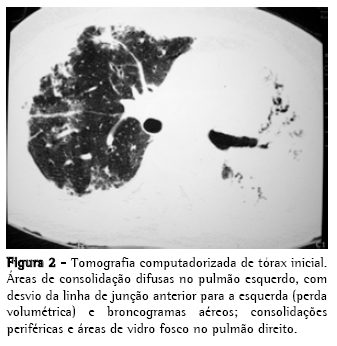

Radiograma e tomografia computadorizada de tórax iniciais, nas Figuras 1 e 2;

Sintomas respiratórios são comuns na SEM e podem estar presentes em até 80% dos pacientes,(14) inclusive como manifestação única. Em uma série de 1.531 casos,(15) tosse ou dispnéia estiveram presentes em 611 deles (59%), e em outro estudo,(16) com 118 pacientes, foram encontrados sintomas respiratórios em 64%, alterações radiológicas em 16% e derrames pleurais em 15%. O acometimento pulmonar confere pior prognóstico e alguns pacientes podem evoluir para insuficiência respiratória aguda.(3,4,17) Os exames complementares, em geral, evidenciam leucocitose e eosinofilia (valores superiores a 3.000/mm3 são mais sugestivos).(11) O radiograma de tórax pode ser normal, apresentar opacidades intersticiais lineares ou reticulonodulares, consolidações pulmonares difusas e derrame pleural.(3,4,10) Os derrames pleurais podem aparecer em até um terço dos casos, e geralmente são exsudatos eosinofílicos.(4,10,16)

De um total de 12 casos relatados, cinco foram submetidos à tomografia de tórax.(4,17,18) Em quatro pacientes foram detectadas consolidações, em geral focais e de predomínio basal, em um paciente foi detectado derrame pleural e em um paciente foram descritos apenas nódulos peribronquiolares difusos. Não houve relatos de consolidações extensas. O pequeno número de pacientes não nos permite estabelecer um padrão, embora consolidações tenham sido encontradas em 80% dos pacientes.